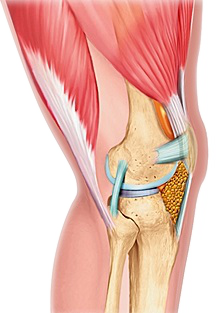

Les ménisques sont des fibro-cartilages interposés de chaque côté des compartiments interne et externe du genou. En forme de croissant ou de quartier de pomme, ils sont solidement attachés en périphérie à l'enveloppe capsulaire et à leurs extrémités antérieure et postérieure au centre du tibia (Figure 1).

En coupe transversale, les ménisques ont une forme triangulaire avec une pér iphérie plus large et bien vascularisée (zone rouge) et un bord libre plus mince et non vascularisé (zone blanche).

De consistance élastique, ils jouent un rôle d'amortissement des contraintes mécaniques et protègent ainsi le cartilage de l'usure ou arthrose. De par leur forme de cale, ils participent avec les ligaments croisés et périphériques à la stabilité du genou.

Figure 1 : anatomie des ménisques (à gauche) et vascularisation périphérique sur une coupe transversale (à droite)